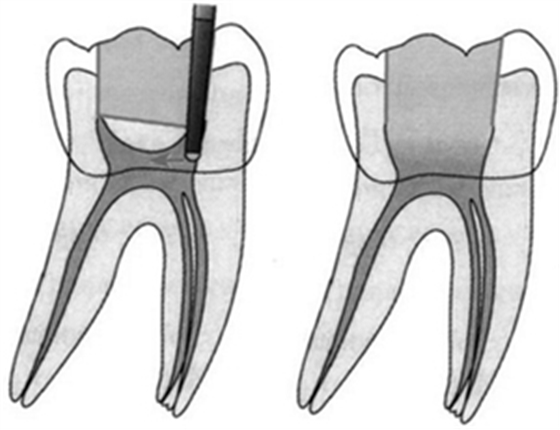

“G型擴孔鉆預(yù)備:應(yīng)用GG鉆預(yù)備根管冠2/3可獲得良好的根管冠部通道。GG鉆進人根管前,一定要用10#或l5#根管銼探查和通暢根管,如果GG鉆1#進入根管有困難時,應(yīng)初步預(yù)備根管,再使用GG鉆進入。一般來說,GGl#進入根管l6~17mm;GG2#,GG3#后退2~3mm;GG4#進入根管口下2~3mm;GG5#,GG6#僅作根管口以上部分預(yù)備,便于髓腔與根管口形成直線通道。GG鉆勿進入根管的深部,避免過度去除牙本質(zhì),造成根管壁的薄弱,形成穿孔或瓶頸樣預(yù)備(見下圖)”

圖 根管帶狀側(cè)穿(stripping,lateral wall perforation)

圖 根管的瓶頸樣預(yù)備(右圖)